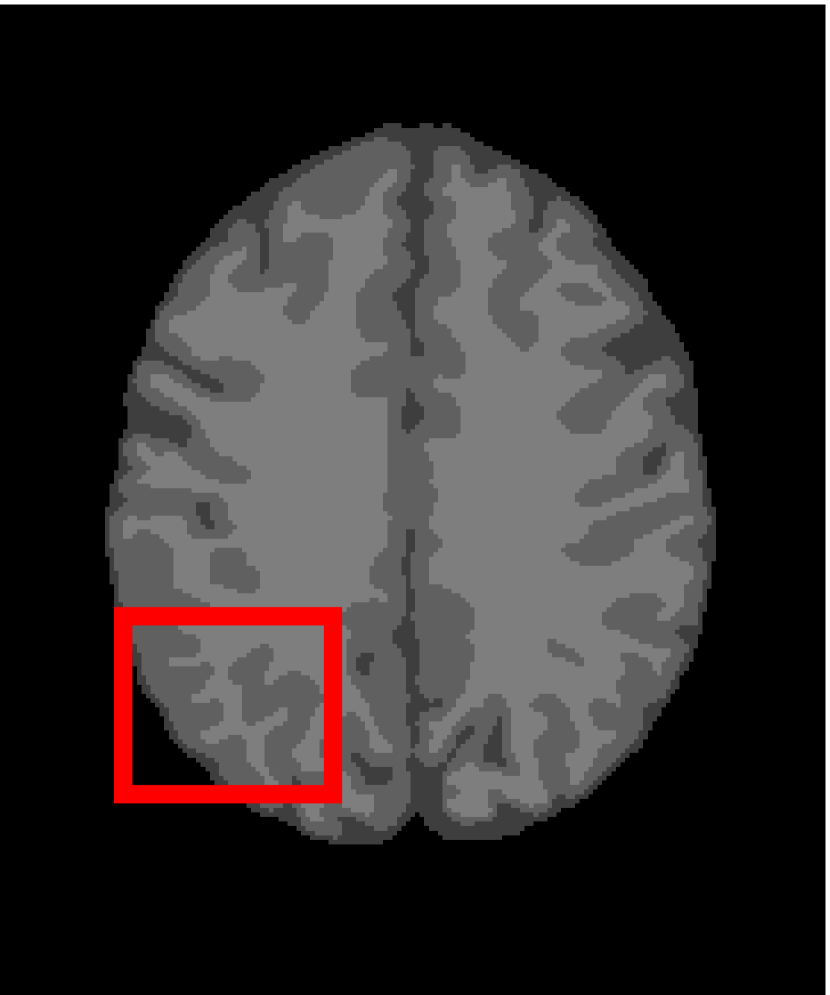

4.4.2 Results on Medical Images

Next, we representatively segment five medical images from BrianWeb. They are represented as five slices in the axial plane with a sequence of 70, 80, 90, 100 and 110, which are generated by T1 modality with slice thickness of 1mm resolution, 9% noise and 20% intensity non-uniformity. Here, we set c=4𝑐4c=4 for all cases. The comparison between WRFCM and its peers are shown in Fig. 9 and Table II. The best values are in bold.

Figure 9: Segmentation results on five medical images. The parameter: ϕ=5.35italic-ϕ5.35\phi=5.35. From top to bottom: noisy images, ground truth, and results of FCM_S1, FCM_S2, FLICM, KWFLICM, FRFCM, WFCM, DSFCM_N, and WRFCM.

TABLE II: Segmentation performance (%) on medical images in BrianWeb

Algorithm Fig. 9 column 1 Fig. 9 column 2 Fig. 9 column 3 Fig. 9 column 4 Fig. 9 column 5

SA SDS MCC SA SDS MCC SA SDS MCC SA SDS MCC SA SDS MCC

FCM_S1 75.756 97.852 96.225 75.026 98.109 96.656 79.792 98.452 97.334 81.887 98.614 97.680 81.869 94.254 90.947

FCM_S2 75.769 98.119 96.664 74.970 98.176 96.765 79.886 98.458 97.338 82.073 98.625 97.695 81.788 98.223 97.195

FLICM 74.998 98.070 96.568 74.185 98.122 96.660 79.099 98.515 97.432 81.447 98.627 97.691 81.668 98.273 97.260

KWFLICM 74.840 98.259 96.878 73.839 97.860 96.190 79.560 98.453 97.316 81.887 98.482 97.443 81.370 98.297 97.286

FRFCM 75.853 97.620 95.775 75.514 97.660 95.830 80.283 98.278 97.013 81.852 98.319 97.171 81.666 98.079 96.945

WFCM 75.507 97.124 94.957 74.471 97.213 95.045 79.316 97.845 96.283 81.358 97.546 95.211 81.452 95.247 92.501

DSFCM_N 76.400 92.325 86.262 75.288 91.574 85.095 79.861 97.678 95.996 81.831 93.304 88.829 81.750 94.302 91.024

WRFCM 82.317 98.966 98.147 82.141 98.298 96.970 83.914 98.963 98.202 83.533 99.170 98.603 84.615 98.429 97.511

By a view of the marked red square in Fig. 9, we find that FCM_S1, FCM_S2, FLICM, KWFLICM and DSFCM_N are vulnerable to noise and intensity non-uniformity. They give rise to the change of topological shapes to some extent. Unlike them, FRFCM and WFCM achieve sufficient noise removal. However, they produce overly smooth contours. Compared with its seven peers, WRFCM can not only suppress noise adequately but also acquire accurate contours. Moreover, it yields the visual result closer to ground truth than its peers. As Table II shows, WRFCM obtains optimal SA, SDS and MCC results for all five medical images. As a conclusion, it outperforms its peers visually and quantitatively.